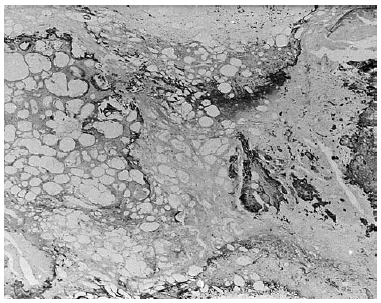

Fig. 1. Estudio histopatológico: imagen panorámica donde se observa una desaparición del panículo adiposo (hematoxilina-eosina).

Fig. 2. Detalle de la histología de la lesión: se advierte hialinización de los adipocitos, esteatonecrosis y depósitos cálcicos con formación de hueso en el tejido celular subcutáneo (hematoxilina-eosina).

Se trata de una mujer de 54 años de edad, con antecedentes de epilepsia temporal derecha y trastornos de la conducta, en tratamiento con carbamazepina, ácido valproico, clorhidrato de trihexifenidilo y diazepam. La paciente presentaba una historia de 3 años de evolución de lesiones nodulares subcutáneas de comienzo en región glútea, con extensión posterior a otras localizaciones. Las lesiones remitían inicial mente, pero volvían a aparecer; en ocasiones se ulceraron y sobreinfectaron, produciéndose fistulización en algunas de ellas. También refería haber presentado artralgias y brotes de inflamación articular con intenso dolor, de predominio en muñecas y articulaciones interfalángicas de las manos. La paciente había realizado tratamiento corticosteroide intermitente sin mejoría. Posteriormente fue ingresada por un cuadro de malestar general, artritis y alteración analítica. En la exploración física se apreciaron a nivel de glúteos, cara, tronco y raíz de extremidades superiores, lesiones nodulares profundas, algunas de ellas ulceradas y otras con eritema en superficie, atrofia, hiperqueratosis e hiperpigmentación en algunos puntos. Presentaba además inflamación, con enrojecimiento e intenso dolor alrededor de las muñecas. Se realizaron dos biopsias cutáneas, la primera de ellas de la región deltoidea, donde se observaba una paniculitis con imágenes de vasculitis y focos de calcificación, con los septos ensanchados y parcialmente hialinizados. La segunda biopsia, obtenida de la región glútea, mostraba una piel sin lesiones microscópicas relevantes en la epidermis. En la dermis reticular subyacente se apreciaba una ausencia de anejos cutáneos y un infiltrado inflamatorio linfocitario focal. En el tejido celular subcutáneo existía una esteatonecrosis difusa que afectaba a todo el espesor del lobulillo, con depósito de un material eosinófilo hialino entre los adipocitos, y presencia de amplios focos de calcificación y osificación (figs. 1 y 2). En el hemograma destacaba una hemoglobina de 10,7 g/dl, un hematocrito del 32,3% y una leucopenia de 3.500 leucocitos/μl con 30% de linfocitos. En el estudio inmunológico presentaba anticuerpos antinucleares (ANA) positivos a título de 1/160; anti-ADN nativo 49 (normal < 20) anticardiolipina IgG 45 (normal < 20) e IgM 28 (normal < 15); C3 73 (83-171) y C4 12 (14-38), siendo el resto de parámetros inmunológicos normales. El resto de pruebas complementarias realizadas (bioquímica, sistemático de orina, coagulación, espectro electroforético, Mantoux, etc.) no presentaron alteraciones significativas. Ante estos hallazgos clínicos, histológicos y serológicos se efectuó el diagnóstico de PL asociado a LES, instaurándose tratamiento con cloroquina a una dosis de 250 mg/día y prednisona oral a dosis variables entre 5-10 mg/día. La mayoría de las lesiones cutáneas desaparecieron, dejando cicatriz residual, pero la placa de la región glútea continuó empeorando, se extendió en superficie, se hizo intensamente dolorosa y presentó ocasionalmente signos de infección local, que requirieron tratamiento antibiótico por vía oral. En la exploración física se apreció una placa de gran tamaño, de consistencia leñosa, con algunas zonas de aspecto cicatricial y trayectos fistulosos con material blanquecino en su interior. La lesión producía una intensa retracción del tejido circundante (fig. 3). Se aumentó la dosis de prednisona a 30 mg/48 h. Las pruebas complementarias realizadas a lo largo de la evolución del clínico continuaron mostrando anemia y leucopenia en el hemograma. Ha presentado anticuerpos antiplaquetarios IgG e IgM. Los ANA fueron positivos de forma casi continua, a títulos de hasta 1/1.280, siendo negativos el resto de autoanticuerpos. Las cifras de C4 y CH100 permanecieron dentro de los límites de la normalidad, pero con cifras bajas de C3. En el resto de pruebas realizadas no se detectaron hallazgos significativos. Actualmente la paciente persiste con una única placa de PL en región glútea, sin claros signos de actividad. En la analítica continúa con anemia, leucopenia, ANA positivos y disminución de C3.